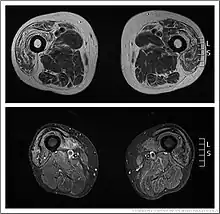

Muscle imaging can help establish the pattern of muscle involvement and selection of a biopsy site.[1]